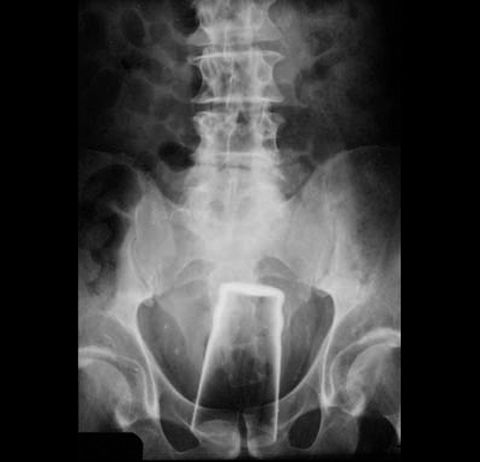

「棒を持ってドブネズミを追い掛け回していた所、油でヌメッていた床で足を滑らした拍子に、その棒がお尻の穴に・・・」

友人の看護師が送信してきたX線画像がテラオソロシイ。

コップ。

カギ。

メガネ。

バズ・ライトイヤー。

直腸だろ。

危険だぞ。

救急救命室で働いてた頃、年に10~20人はこの手の患者が来た。

ビンやらスプーンやらなんでもかんでもって感じ。